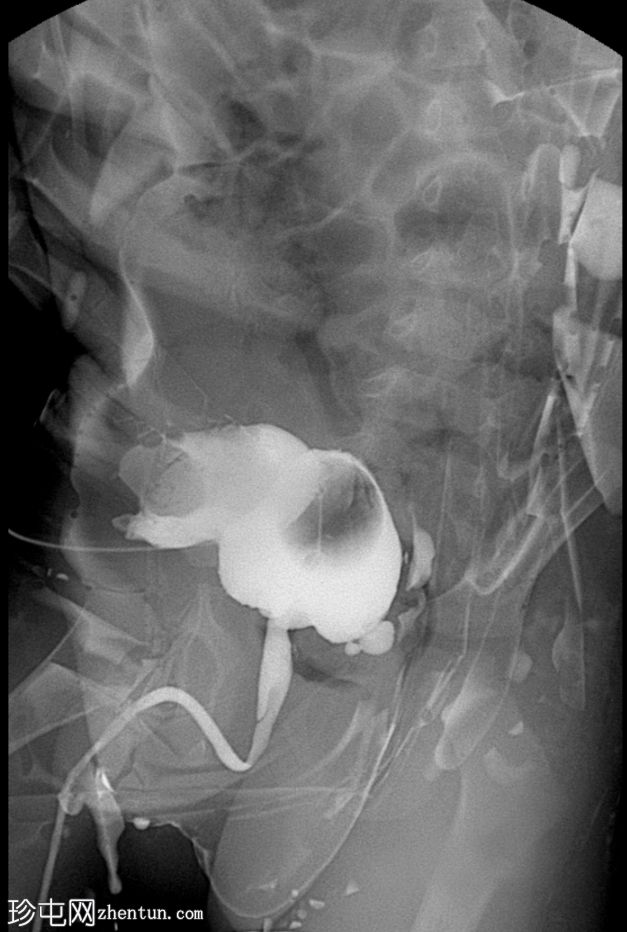

正位片(含Foley导尿管球囊)

可见脐尿管开口通畅;在充盈期,造影剂经脐尿管自由流出,导致膀胱充盈不足。经脐尿管开口置入Foley导尿管并充盈球囊;然而,造影剂持续渗漏,膀胱充盈仍然不足。

使用纱布进行外部压迫成功阻塞了脐尿管开口,膀胱充盈良好。左侧输尿管和肾盂肾盏系统可见膀胱输尿管反流,符合II/III级VUR。输尿管轮廓正常,无憩室,无管壁增厚。尿道显影正常,未见后尿道瓣膜或狭窄。无肾积水。